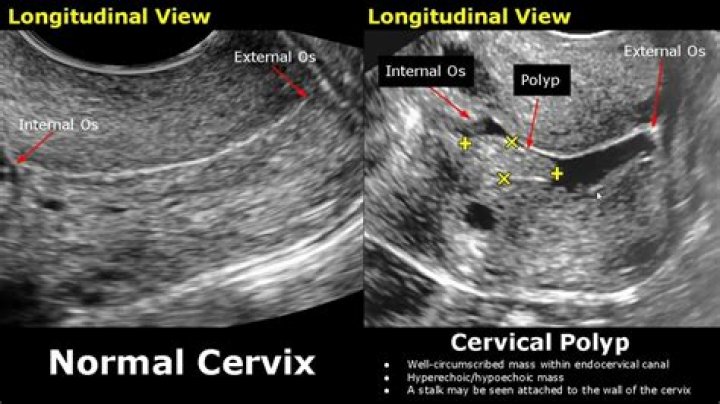

Can cervical polyps be seen on ultrasound?

Cervical polyps are sometimes seen by the doctor during a Pap Smear, endometrial polyps can be seen on ultrasound.